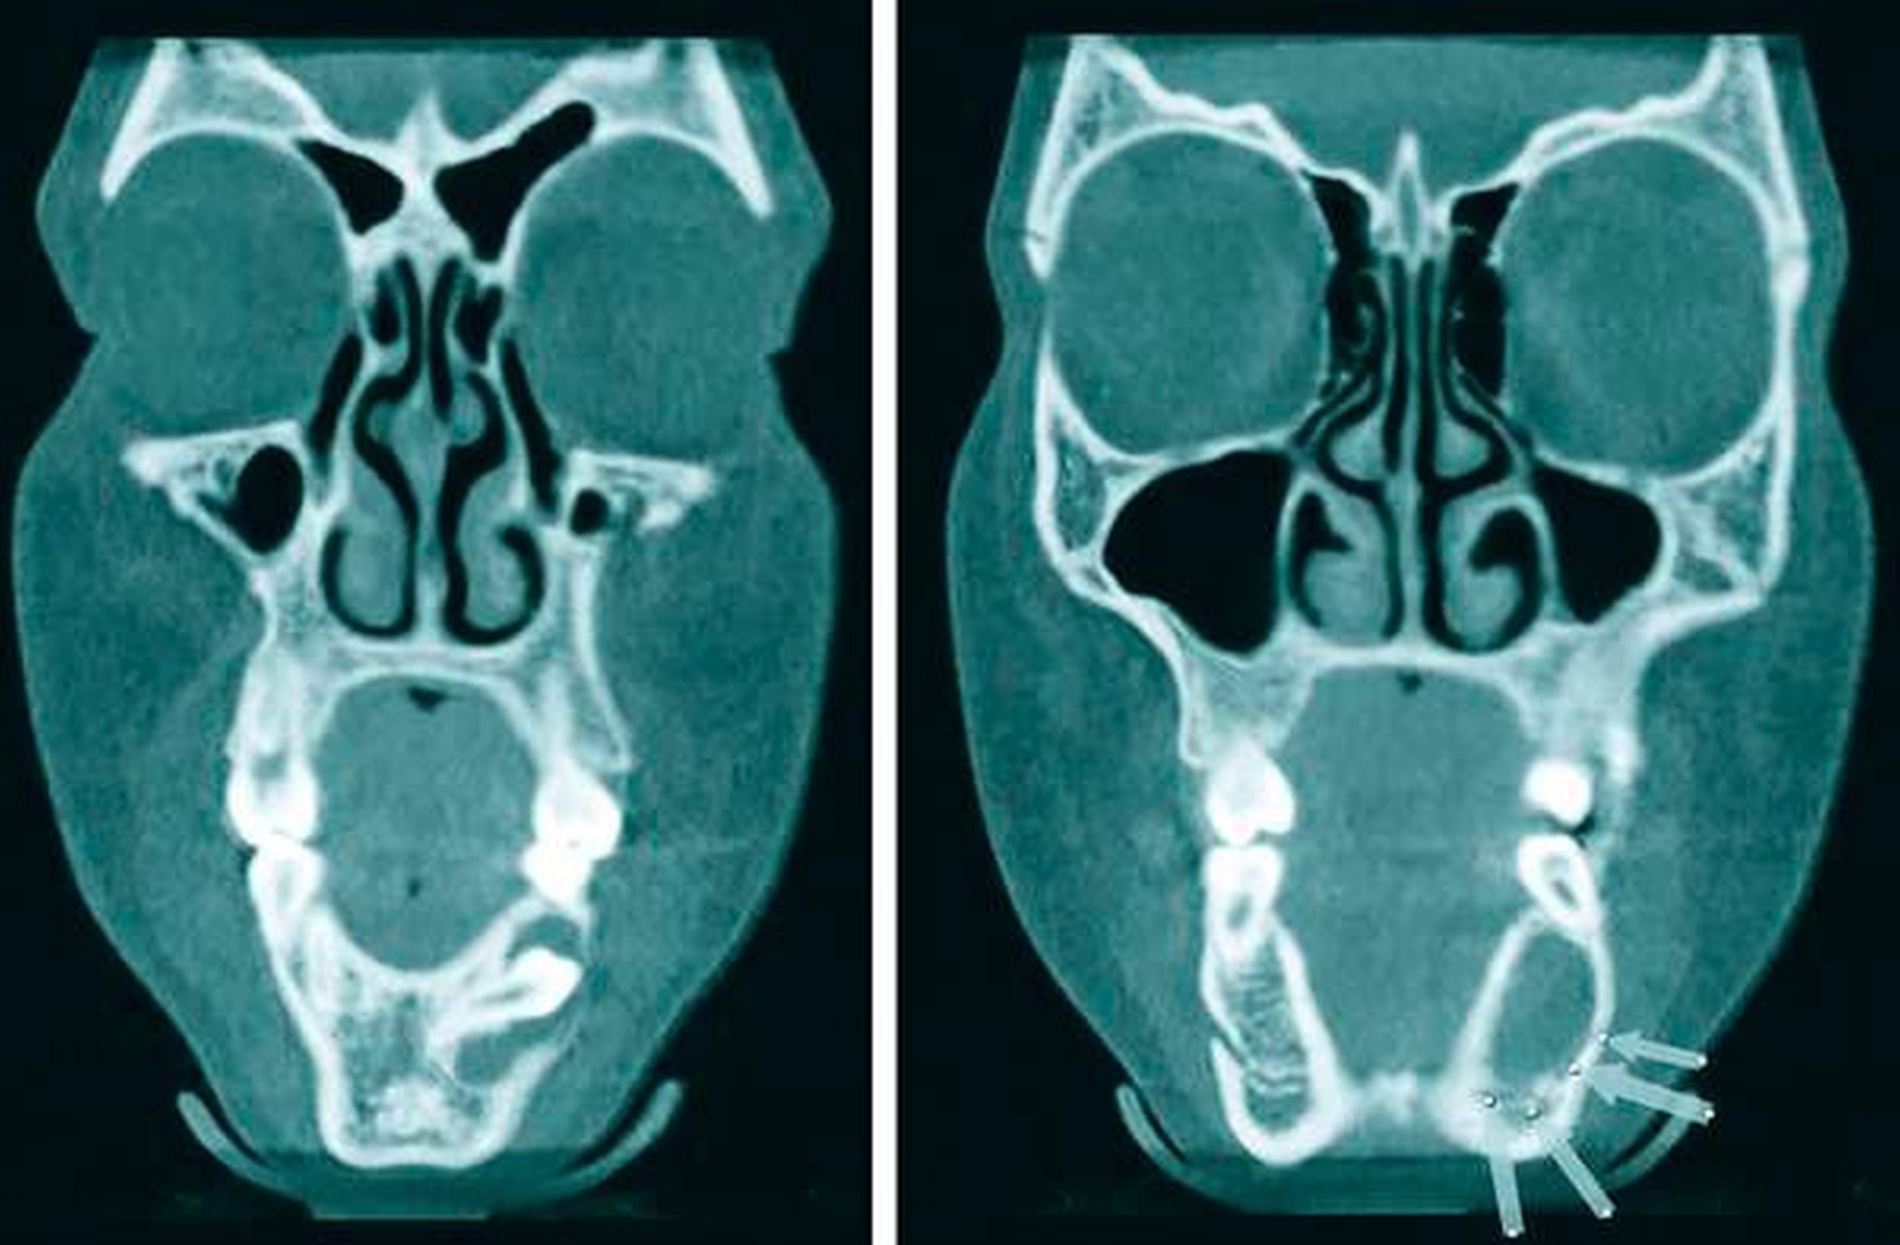

Zur weiteren Therapieplanung wurde ein DVT erstellt, das den persistierenden Zahn 74 zeigte sowie eine große, mutmaßlich follikuläre Zyste, die sich circulär um den Zahn 34 ausdehnt, der seinerseits horizontal verlagert lag und nach schräg distal ausgerichtet war. Der N. alveolaris inferior wurde nach kaudal durch die Raumforderung verdrängt. Die Wurzel lag nach mesial und in der lingualen Kortikalis, die Krone nach vestibulär und distal in das Zystenlumen reichend (Abbildungen 5a bis 5c).